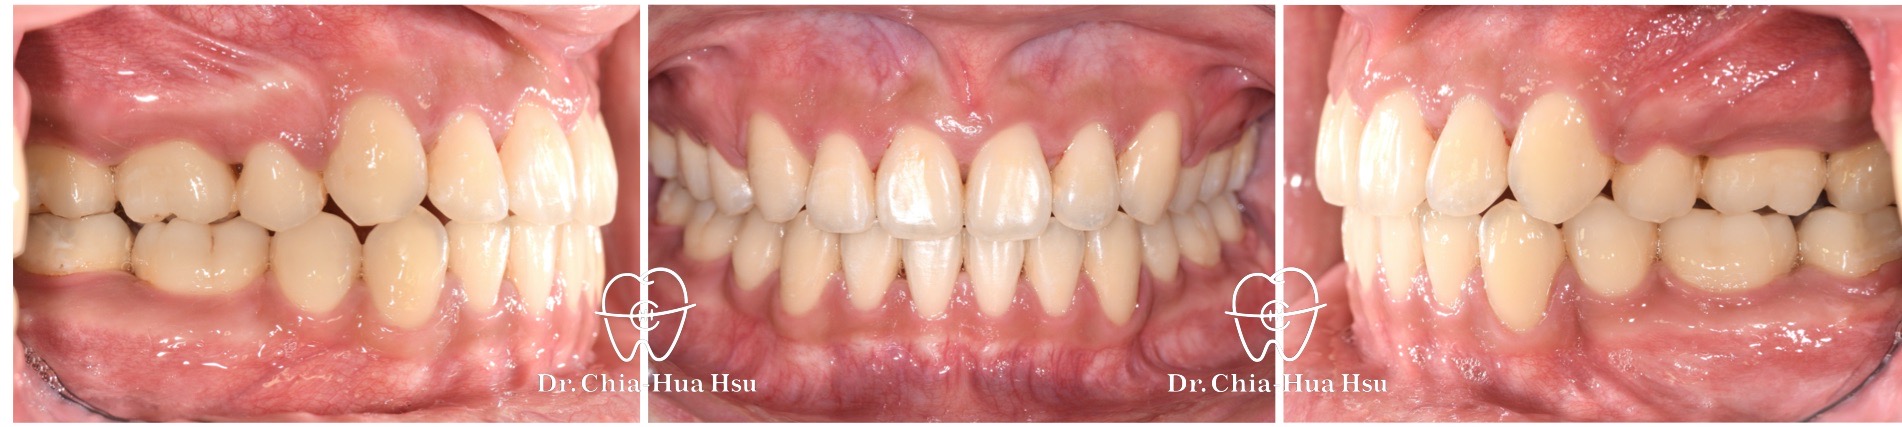

- 風趣幽默的20歲黃同學因為暴牙來院求診,由於患者下巴後縮又暴牙屬於複雜困難病例,還好病人十分配合療程,在許醫師悉心治療下,經歷兩年左右,讓治療順利完成。

- 病患主訴:暴牙、嘴凸、中線歪斜。

- 問題分析:患者是嚴重的骨骼二類咬合(Skeletal Class II)、下巴後縮、暴牙以及齒列不整齊。

- 治療方式:使用傳統金屬矯正器,並拔除四顆小臼齒,配合多支暫時性迷你骨釘來完成治療。

- 治療時間:2 年 2 個月。

- 治療結果:齒列排齊,外觀明顯改善,笑容更自信。

治療前

治療後